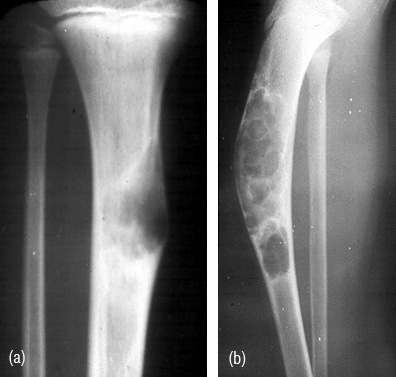

Osteofibrous dysplasia

It is also named as Kempson-campanacci lesion. It commonly involves tibia shaft. Radiologically, an elongated lytic lesion with areas of sclerosis and anterior bowing (Figure 3abc).

Figure 3: (a) osteofibrous dysplasia involving mid tibia. (b, c) 14-year-old girl - Osteofibrous dysplasia involving the entire tibia.

Fibrous dysplasia

Most common bone dysplasia where fibrous aberration occurs replacing the bone as a developmental error. A defective gene exists in the cells that form bone and other tissues. It may be monostotic and may simulate a benign or malignant bone tumor. However, the radiological features such as transitional zone in an expanding lytic area, thick sclerotic rind, ground glass appearance of the matrix and local deformity of bone differentiate from benign bone tumors (Figure 4abcd). On rare occasions chondroid type of calcifications may be seen. Pathological fractures may occur and the lesion may be aggressive simulating malignancy.

Figure 4: (a) Fibrous dysplasia of rib, (b) neck of femur with pathological fracture, (c) aggressive lesion simulating cartilagenous lesion, (d) Sessile exostosis simulating fibrous dysplasia.